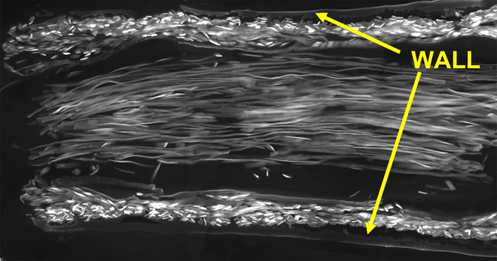

Imagem de microscopia eletrónica de varrimento que mostra uma secção longitudinal de um conduto de seda contendo fibras luminais de seda que orientam o crescimento nervoso. Imagem de Newrotex Ltd

Uma equipa da Universidade de Oxford e da Medical University of Vienna desenvolveu um conduto híbrido feito com dois tipos de seda. A parede externa é construída a partir da fibroína do bicho-da-seda (Bombyx mori), um material já usado em suturas médicas e implantes biodegradáveis, conhecido pela sua porosidade e compatibilidade celular. No interior, o tubo é preenchido com fibras de seda de aranha (Trichonephila edulis), dispostas longitudinalmente como guias microscópicas que orientam o crescimento das células nervosas.

Nos testes laboratoriais com ratos, verificou-se que as células de Schwann, células do sistema nervoso periférico responsáveis por envolver os axónios e facilitar a regeneração nervosa, aderiam às fibras de seda de aranha e migravam a velocidades superiores a 1,1 mm por dia, orientando o crescimento dos axónios até à reconexão das extremidades do nervo. Este comportamento não ocorreu em tubos que não continham estas fibras internas, o que confirma a importância da arquitetura híbrida. Além disso, o material revelou elevada biocompatibilidade e capacidade de degradação, evitando reações imunológicas graves e dispensando uma segunda cirurgia para a sua remoção.